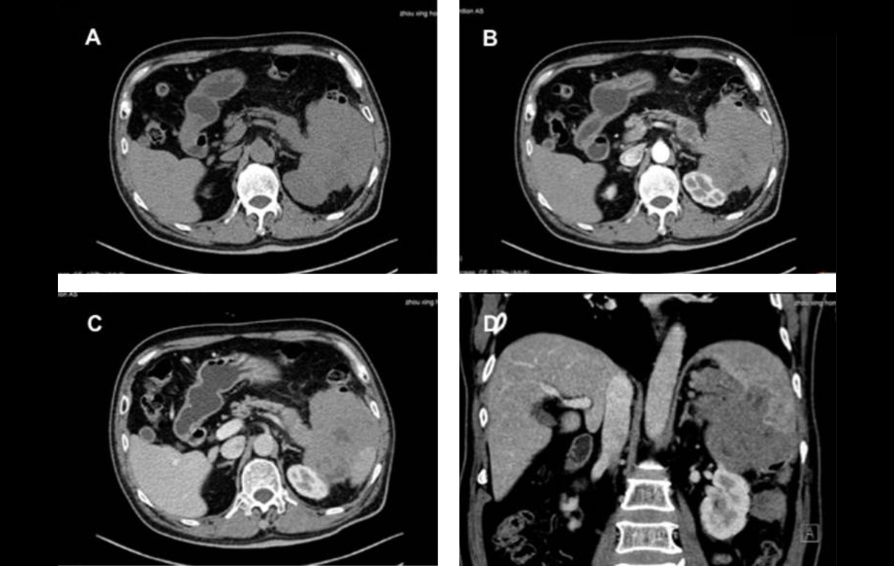

??? US, CEUS, CT ? ?? PET/CT ??? ???? ? ??? Fig 1-3? ????.

?? ?? ??? ??????? ????(nonspecific) ??? ???(primary pancreatic cancer)?? ????? ??? ?? ???(primary pancreatic lymphoma)? ?????(Burkitt lymphoma)? ???? ??? ?? ?? ??(pancreatic mass)? ?? ???????(ultrasound guided biopsy)? ???????.

??? ?????? R-Hyper-CVAD-A ????? ???? ??? CT ??? ?? ?? ??? ??? ??? ?? ?? ? ? ????. (Fig 4 A-C). ??? ???? ??? ?? ??? ??????.